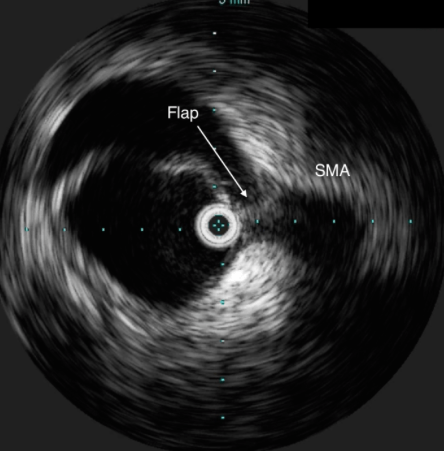

This technology (pictured here) is a useful tool in treatment of aortic dissection.

What is intravascular ultrasound (IVUS)?